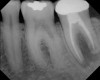

Figure 8  Clinical case of internal root resorption that was treated by orthograde root canal therapy.

Figure 8